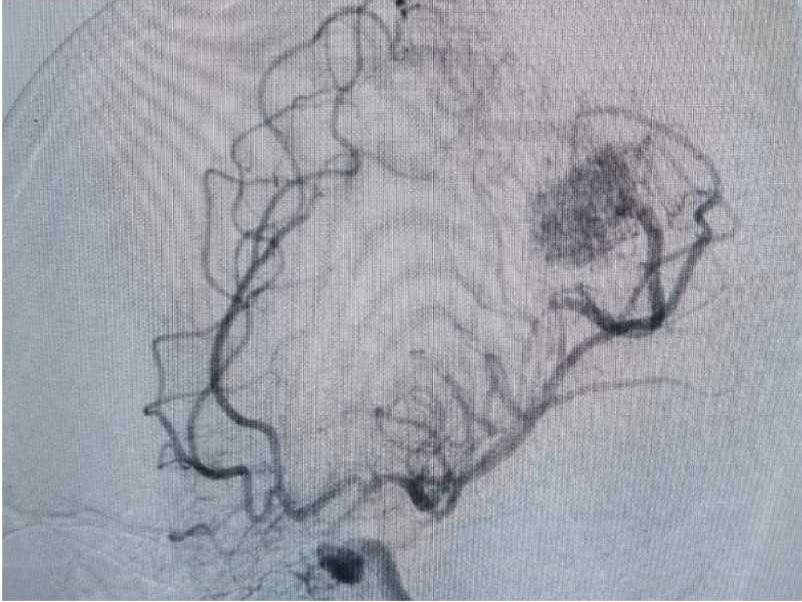

行DSA检查

显示畸形血管团为20*23mm,多支动脉参与供血,引流至上矢状窦。